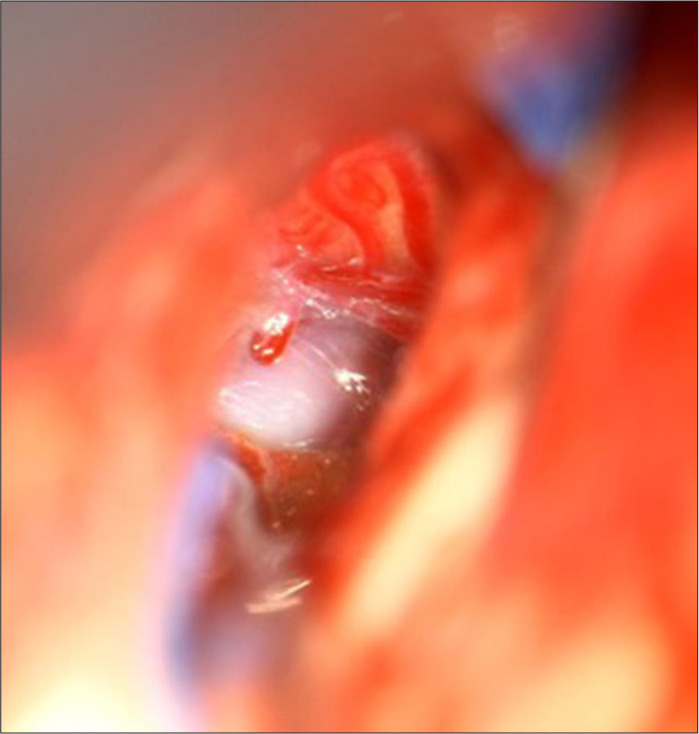

Case description: A 12-year-old girl presented with progressive gait disturbances, disequilibrium, diplopia due to right-sided abducens paresis, left-sided facial paresis (HB grade II), headaches, nausea, and vomiting over the past 6 months. Magnetic resonance imaging (MRI) revealed an intrinsic lesion of the brainstem not present on MRI 4 years prior. A microsurgical gross total resection, including resection of cyst wall, was performed. The pathology report diagnosed the lesion as an epidermoid cyst. The patient improved significantly after resection.